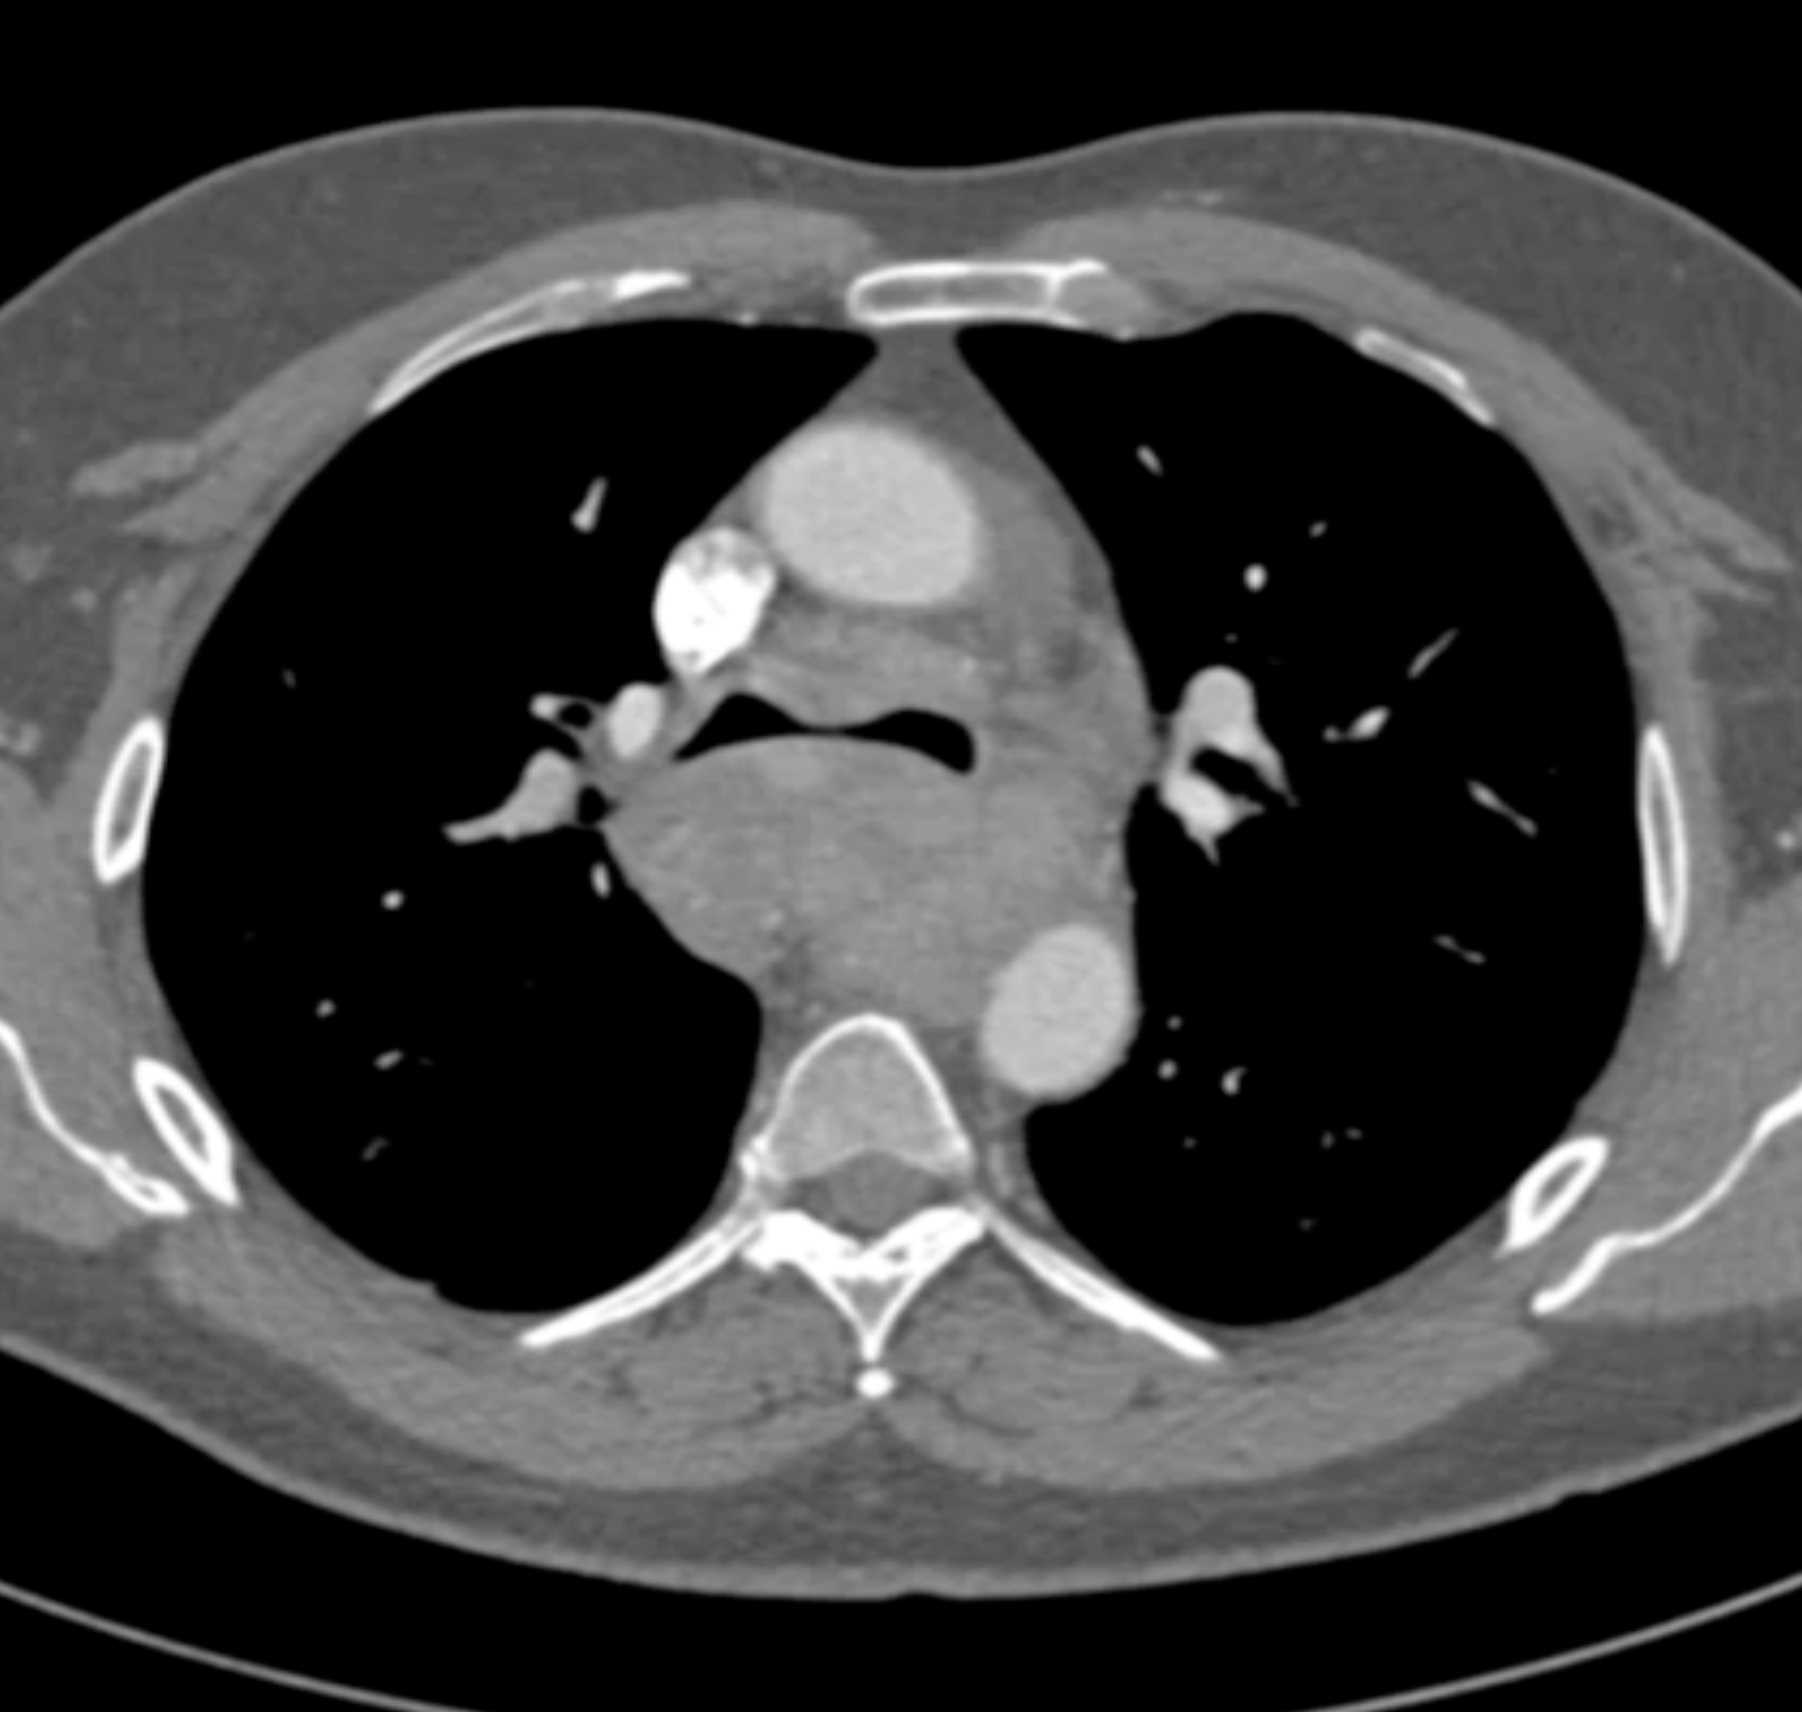

Fibrosing Mediastinitis